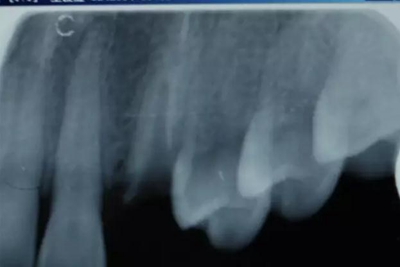

病例一 女性,20歲,大學生,要求補牙,檢查口內(nèi)可見A6大面積缺損,近中牙齦息肉,拍X片,根管充填物略差,但根周未見明顯陰影,口內(nèi)檢查無叩痛。建議患者冠延長手術+高嵌體修復。

患牙遠中邊緣嵴完整,強度沒有降低,故擬保留遠中邊緣嵴,高嵌體修復。首先去除腐質(zhì)及原墊底材料,流體樹脂+3M Z350XT樹脂墊底。局麻下行冠延長手術。在此需要提及個人的一個觀點。冠延長手術原則上要求3-6個月以上才能永久修復。但是個人喜歡后牙肩臺建立在齦上,所以修復后的修復體邊緣位于牙齦上方1mm,對牙周的愈合影響較?。ㄈ绻麨辇l下邊緣則要慎重),故該患者術中按照齦上邊緣的設計進行冠延長手術。以下為術中: